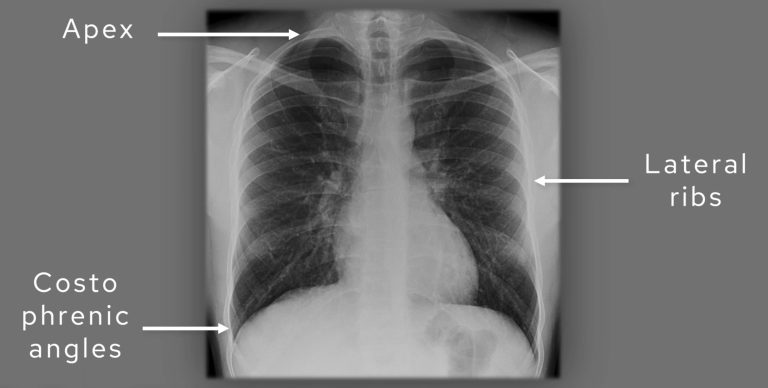

Before you jump into assessing your film, take a look at this annotated view of a PA (posterior-anterior) chest X-Ray looking at some of the basic anatomy.

Annotated view of a PA adult chest X-Ray

C: Coverage

Finally, check coverage. A decent chest film should include the apices with the first ribs, the lateral chest walls, and both costophrenic angles. If any of those are cut off, you risk missing pathology such as a tiny apical pneumothorax or a small effusion.

Assess coverage: check to see if the apices, lateral ribs and costophrenic angles are covered.